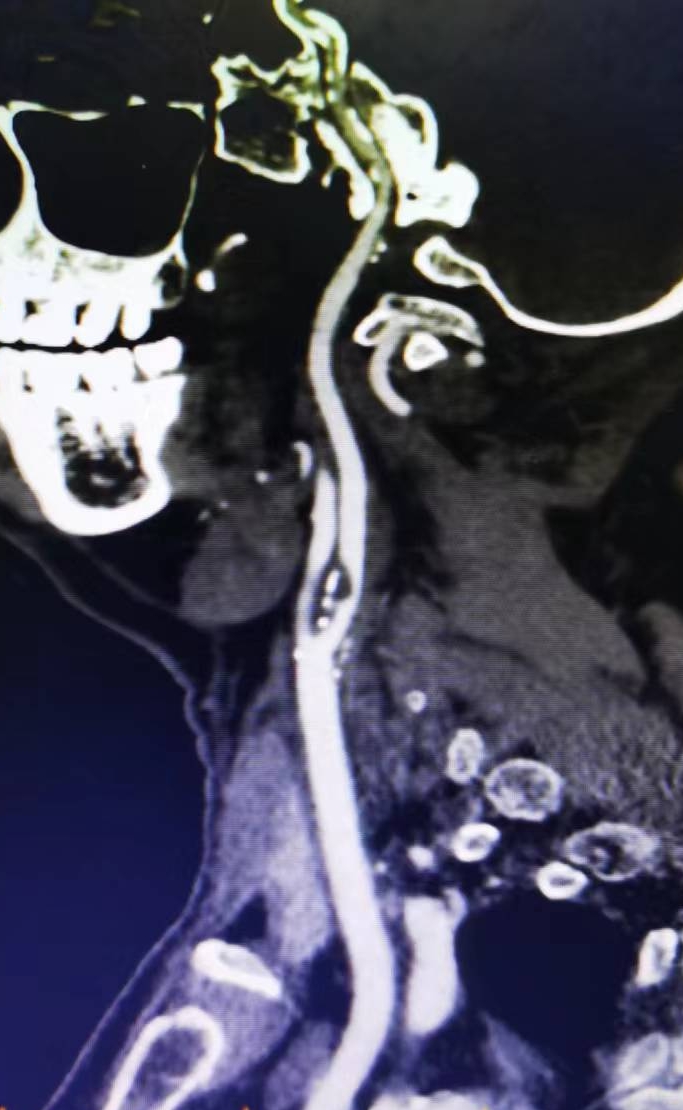

患者男性,70岁,体检发现双侧颈内动脉重度狭窄,1月前行右侧颈内动脉支架成形术,现为治疗左侧颈内动脉狭窄入院。既往高血压病史30年,口服硝苯地平控释片降压,血压控制130/80mmHg。

2、左侧颈内动脉从CTA看狭窄合并软斑,具备介入治疗指征。